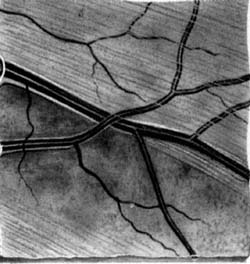

Buňky v centrální části sítnice se začínají diferencovat nejdříve a již za týden jejich výběžky dosahují až k terči. Tak vzniká základ makulopapilárního svazku. Během dalších několika dnů se diferencují gangliové buňky v perifernějších oblastech sítnice. Těm, které rostou z temporální strany, překáží v cestě ke zrakovému nervu již vytvořený makulopapilární svazek a musí jej obloukovitě obejít. Vlákna rostoucí z gangliových buněk z nasální strany takovou překážku na cestě nemají a jejich průběh ke zrakovému je přímý. Tímto způsobem během několika dní vzniká vrstva nervových vláken. Její uspořádání nám umožňuje pochopit lokalizaci skotomů zorného pole.

Výpadky nervových vláken na sítnici a graficky na perimetru podle Minclera

Korelace lokálního výpadku nervových vláken se změnami zorného pole dle Minclera

Když exkavace zasahuje až okraji terče dochází k poškození vláken, která vedou až do temporální části sítnice k tělům gangliových buněk, uloženým v sousedství horizontálního švu. Poškození těchto buněk a jejich axonů se projeví nasálním skokem s arkuátním Bjerumovým skotomem.

Pokud exkavace nedosahuje k samému okraji terče (miskovité exkavace), svědčí to pro poškození vláken z povrchnější vrstvy, které směřují k gangliovým buňkám uloženým paracentrálně – periferně od makulopapilárního svazečku. Poškození těchto buněk a jejich axonů se projeví paracentrálními skotomy.